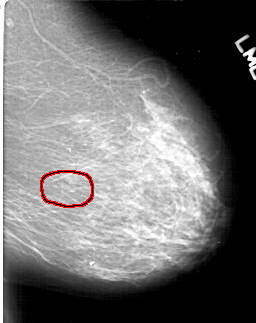

D_4198_1.LEFT_MLO

LEFT_MLO LINES 5476 PIXELS_PER_LINE 4351 BITS_PER_PIXEL 12 RESOLUTION 43.5 OVERLAY

FILE: D_4198_1.LEFT_MLO.OVERLAY

TOTAL_ABNORMALITIES 1

ABNORMALITY 1

LESION_TYPE CALCIFICATION TYPE ROUND_AND_REGULAR-PLEOMORPHIC DISTRIBUTION CLUSTERED

ASSESSMENT 0

SUBTLETY 4

PATHOLOGY BENIGN

TOTAL_OUTLINES 1

BOUNDARY